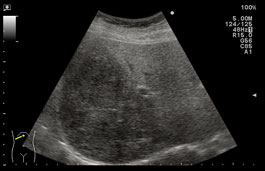

肝内に1cm程度の低エコー小円形の腫瘤が多発し、境界はやや不明瞭である。小型の転移性腫瘍によく見られるエコー像である。本例は肺癌からの転移であった。 |